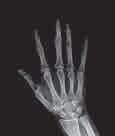

Ултразвучна дијагностика

би се снимила унутрашњост

Ове фреквенције су превисоке да би их људско ухо могло чути. Део ултразвучних таласа, као и свих таласа, при наиласку

тразвучној дијагностици се

рефлексије или еха (одјека) звучних таласа. Ултразвучно снимање је посебно добро у откривању цисти, које су џепови течности у јетри, жлездама